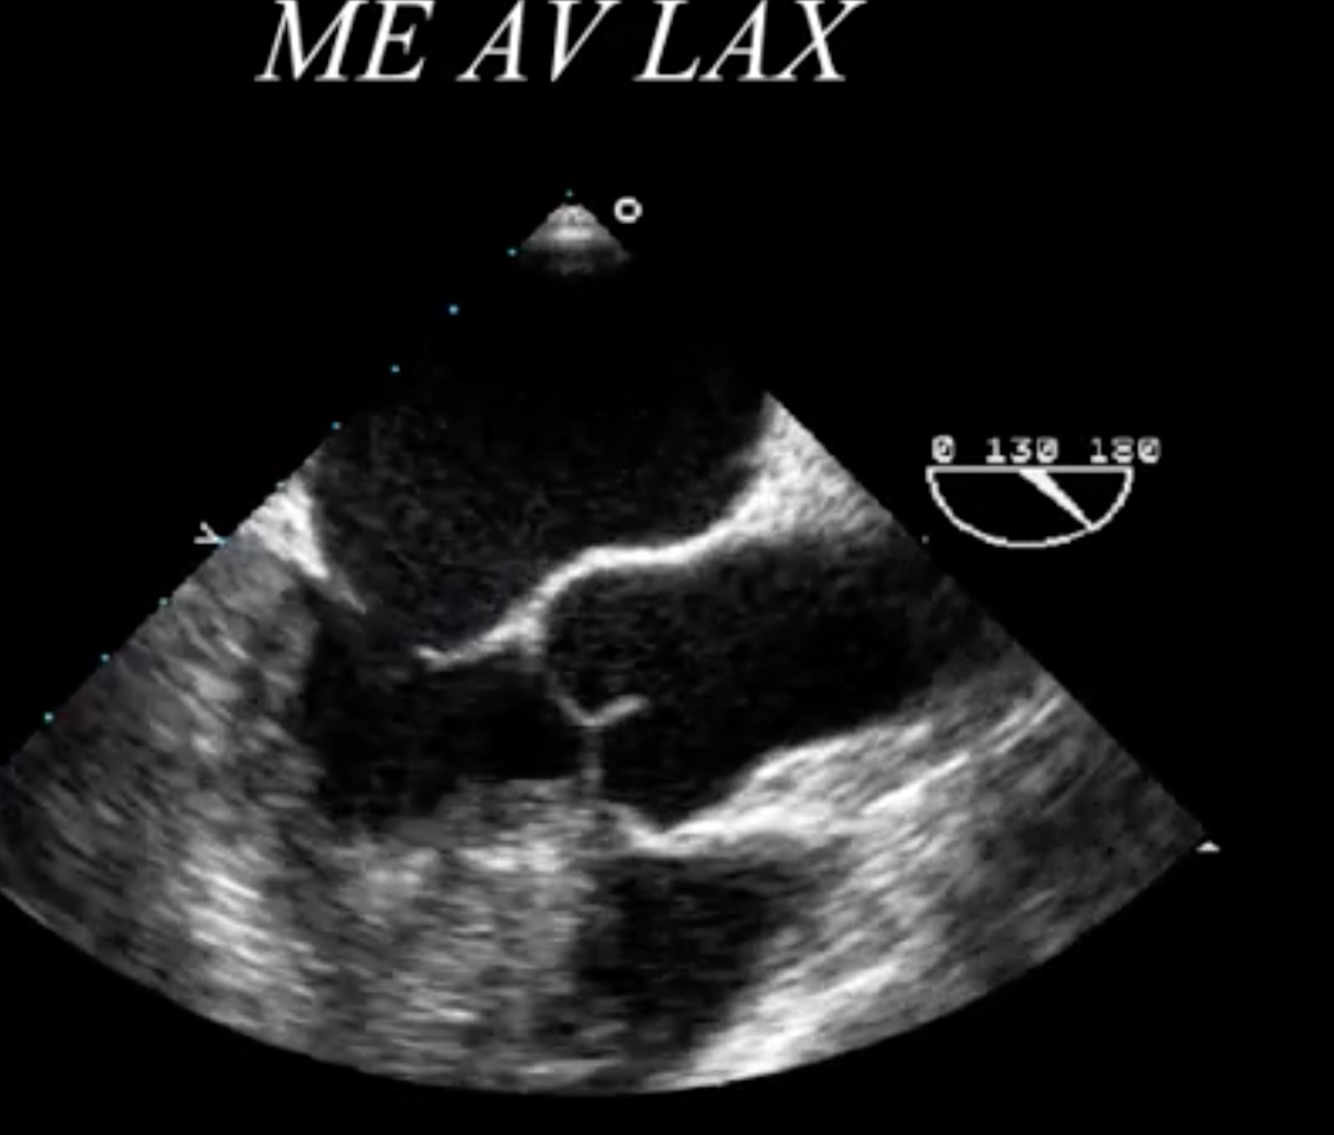

Mid-esophageal Aortic Valve Long Axis

How do you determine which coronary cusp is which in the long axis?

Right Coronary Cusp = Bottom of the Screen

Left or NON Coronary Cusp = Top of the Screen